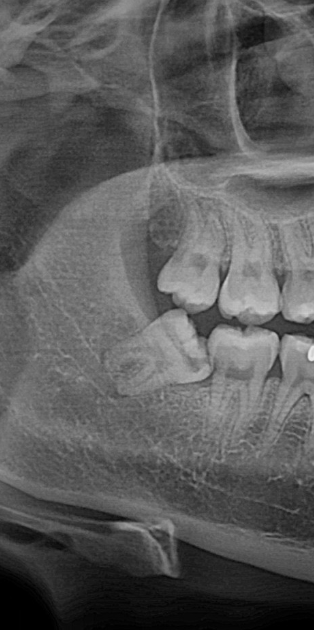

반면 뼈 안에 완전히 파묻혀 있는 사랑니는 이야기가 다릅니다.

잇몸을 절개하고, 이를 조각조각 나눠서 빼내야 하기 때문에 진동도 크고 시술 시간도 길어집니다.

## 누워 있는 사랑니는 왜 더 어렵게 빠지나요?

그런데 사랑니가 옆으로 누워 있으면 나올 방향 자체가 막혀 있습니다. 그대로는 빠질 수가 없는 구조입니다.

그래서 이를 잘라서 일부를 꺼내고, 또 잘라서 꺼내는 방식을 반복해야 합니다.

발치 전 X-ray와 상담을 통해 본인의 사랑니가 어떤 상태인지 먼저 확인하고, 그에 맞는 마취 방법을 선택하시는 것이 가장 현명한 방법입니다.